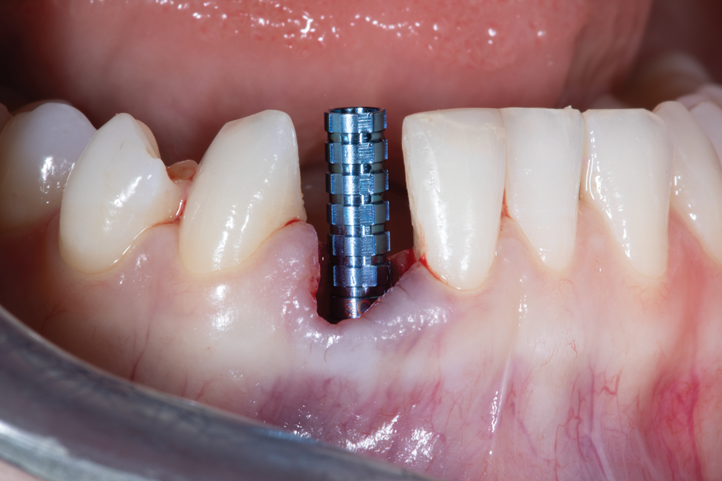

A retrospective evaluation of 128 socket-shield cases in the esthetic zone and posterior sites reported a survival rate of 96.1%. The most common complications noted were internal exposures (exposure of the retained root within the peri-implant sulcus) followed by external exposures (occurring on the external surface of the peri-implant free gingivae) of the retained root shield.64 In reaction to this noted complication, modifications to the original socket-shield technique were subsequently introduced and emphasized a reduced height of the socket-shield remnant to be equal in height to the immediate adjacent bone crest level and then preparation of a chamfer finish to the coronal aspect of the shield's internal dentin surface. This modification was designed to avert the internal exposure of the shield and facilitate fabrication of a prosthetically modified provisional restoration with an "S"-shaped emergence profile thereby enhancing the maximum potential of the resultant soft-tissue infill.65 This modification reduces both internal and external exposures of the socket shields (according to ongoing research by present author HG and colleagues, which is yet unpublished). The technique is depicted in Figure 4 through Figure 10.

Fig 4. Preoperative CBCT cross-sectional view demonstrating very thin buccal cone.

Figure 4

Fig 6. Initial preparation of the buccal aspect of the root to be retained.

Figure 6

Fig 7. Finalized preparation utilizing the PET protocol, with implant placement in the No. 8 (1:1) position. An “S”-shaped chamfer preparation was made internally to the retained buccal portion of the root.

Figure 7

Fig 8. CBCT at 1-year postoperative demonstrated the retention of the buccal portion of the root as well as maintenance of the buccal plate of bone. Beam hardening and volume averaging artifacts can be noted in the CBCT cross-section.

Figure 8